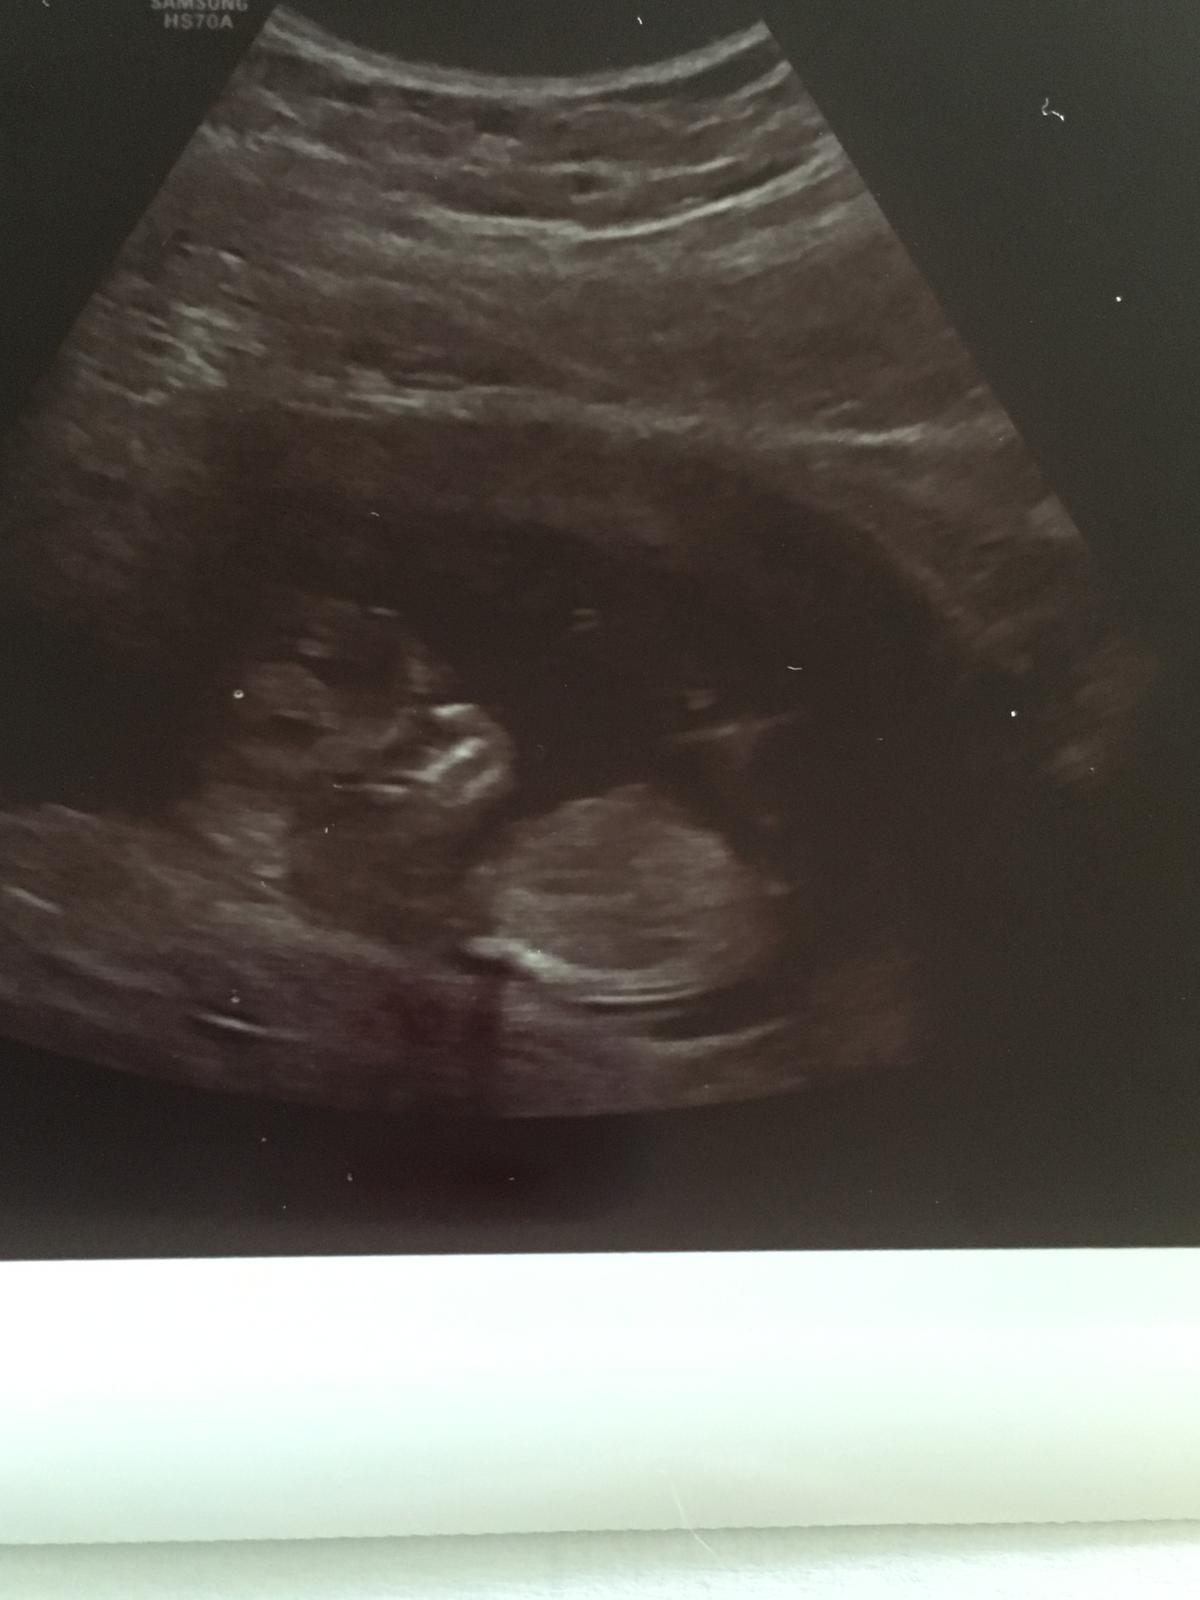

Dle ms dnes 12+5, dle utz 12+6, termin 11.1.2018 zachován.

Crl mimi od hlavičky po zadeček 6,6 Cm, krásně vyrostlo od pátka 🙂 a zase se otočilo 😃

Srdíčko bylo 164 údery za minutu

Šíjové projasnění 1,80 mm

Obvod hlavičky 7,7 cm

Obvod bříška 6,3 cm

Riziko trizometrie 21 1:15110

Riziko trizometrie 18 a 13 <1:20000

Další screening 30.8.

Foto horší, zhoršené akustické podmínky... ale hezky bylo v klidu, že mimi chválila. Pohlaví se neví, nožičky melo mímo nahoru a u sebe. Prý koukala 😃😂 tak to máme prý 50:50

Jinak ho tam v jednu chvíli šťouchla a vyhodilo jednu ručičku, jak kdyby jí řeklo, ať si dá odchod, že nechce být rušeno 😂